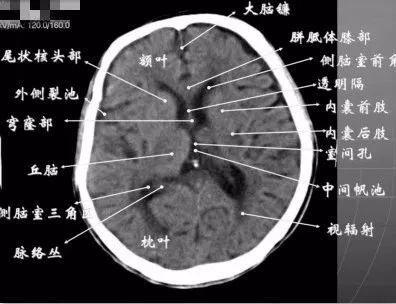

脑ct图片讲解正常,脑ct图片讲解片子

脑ct图片诊断

颅脑ct怎么看?正常和异常影像分别是什么?

影像总结:头颅ct基本知识与常见病变

脑ct图片讲解片子

脑ct图片讲解

正常脑ct图片

脑ct图片讲解诊断

正常脑ct图片大全

正常脑ct图片头颅

正常人脑部ct图片

新手看脑部ct片图解

脑ct讲解

脑ct正常

新手看头颅ct片图解